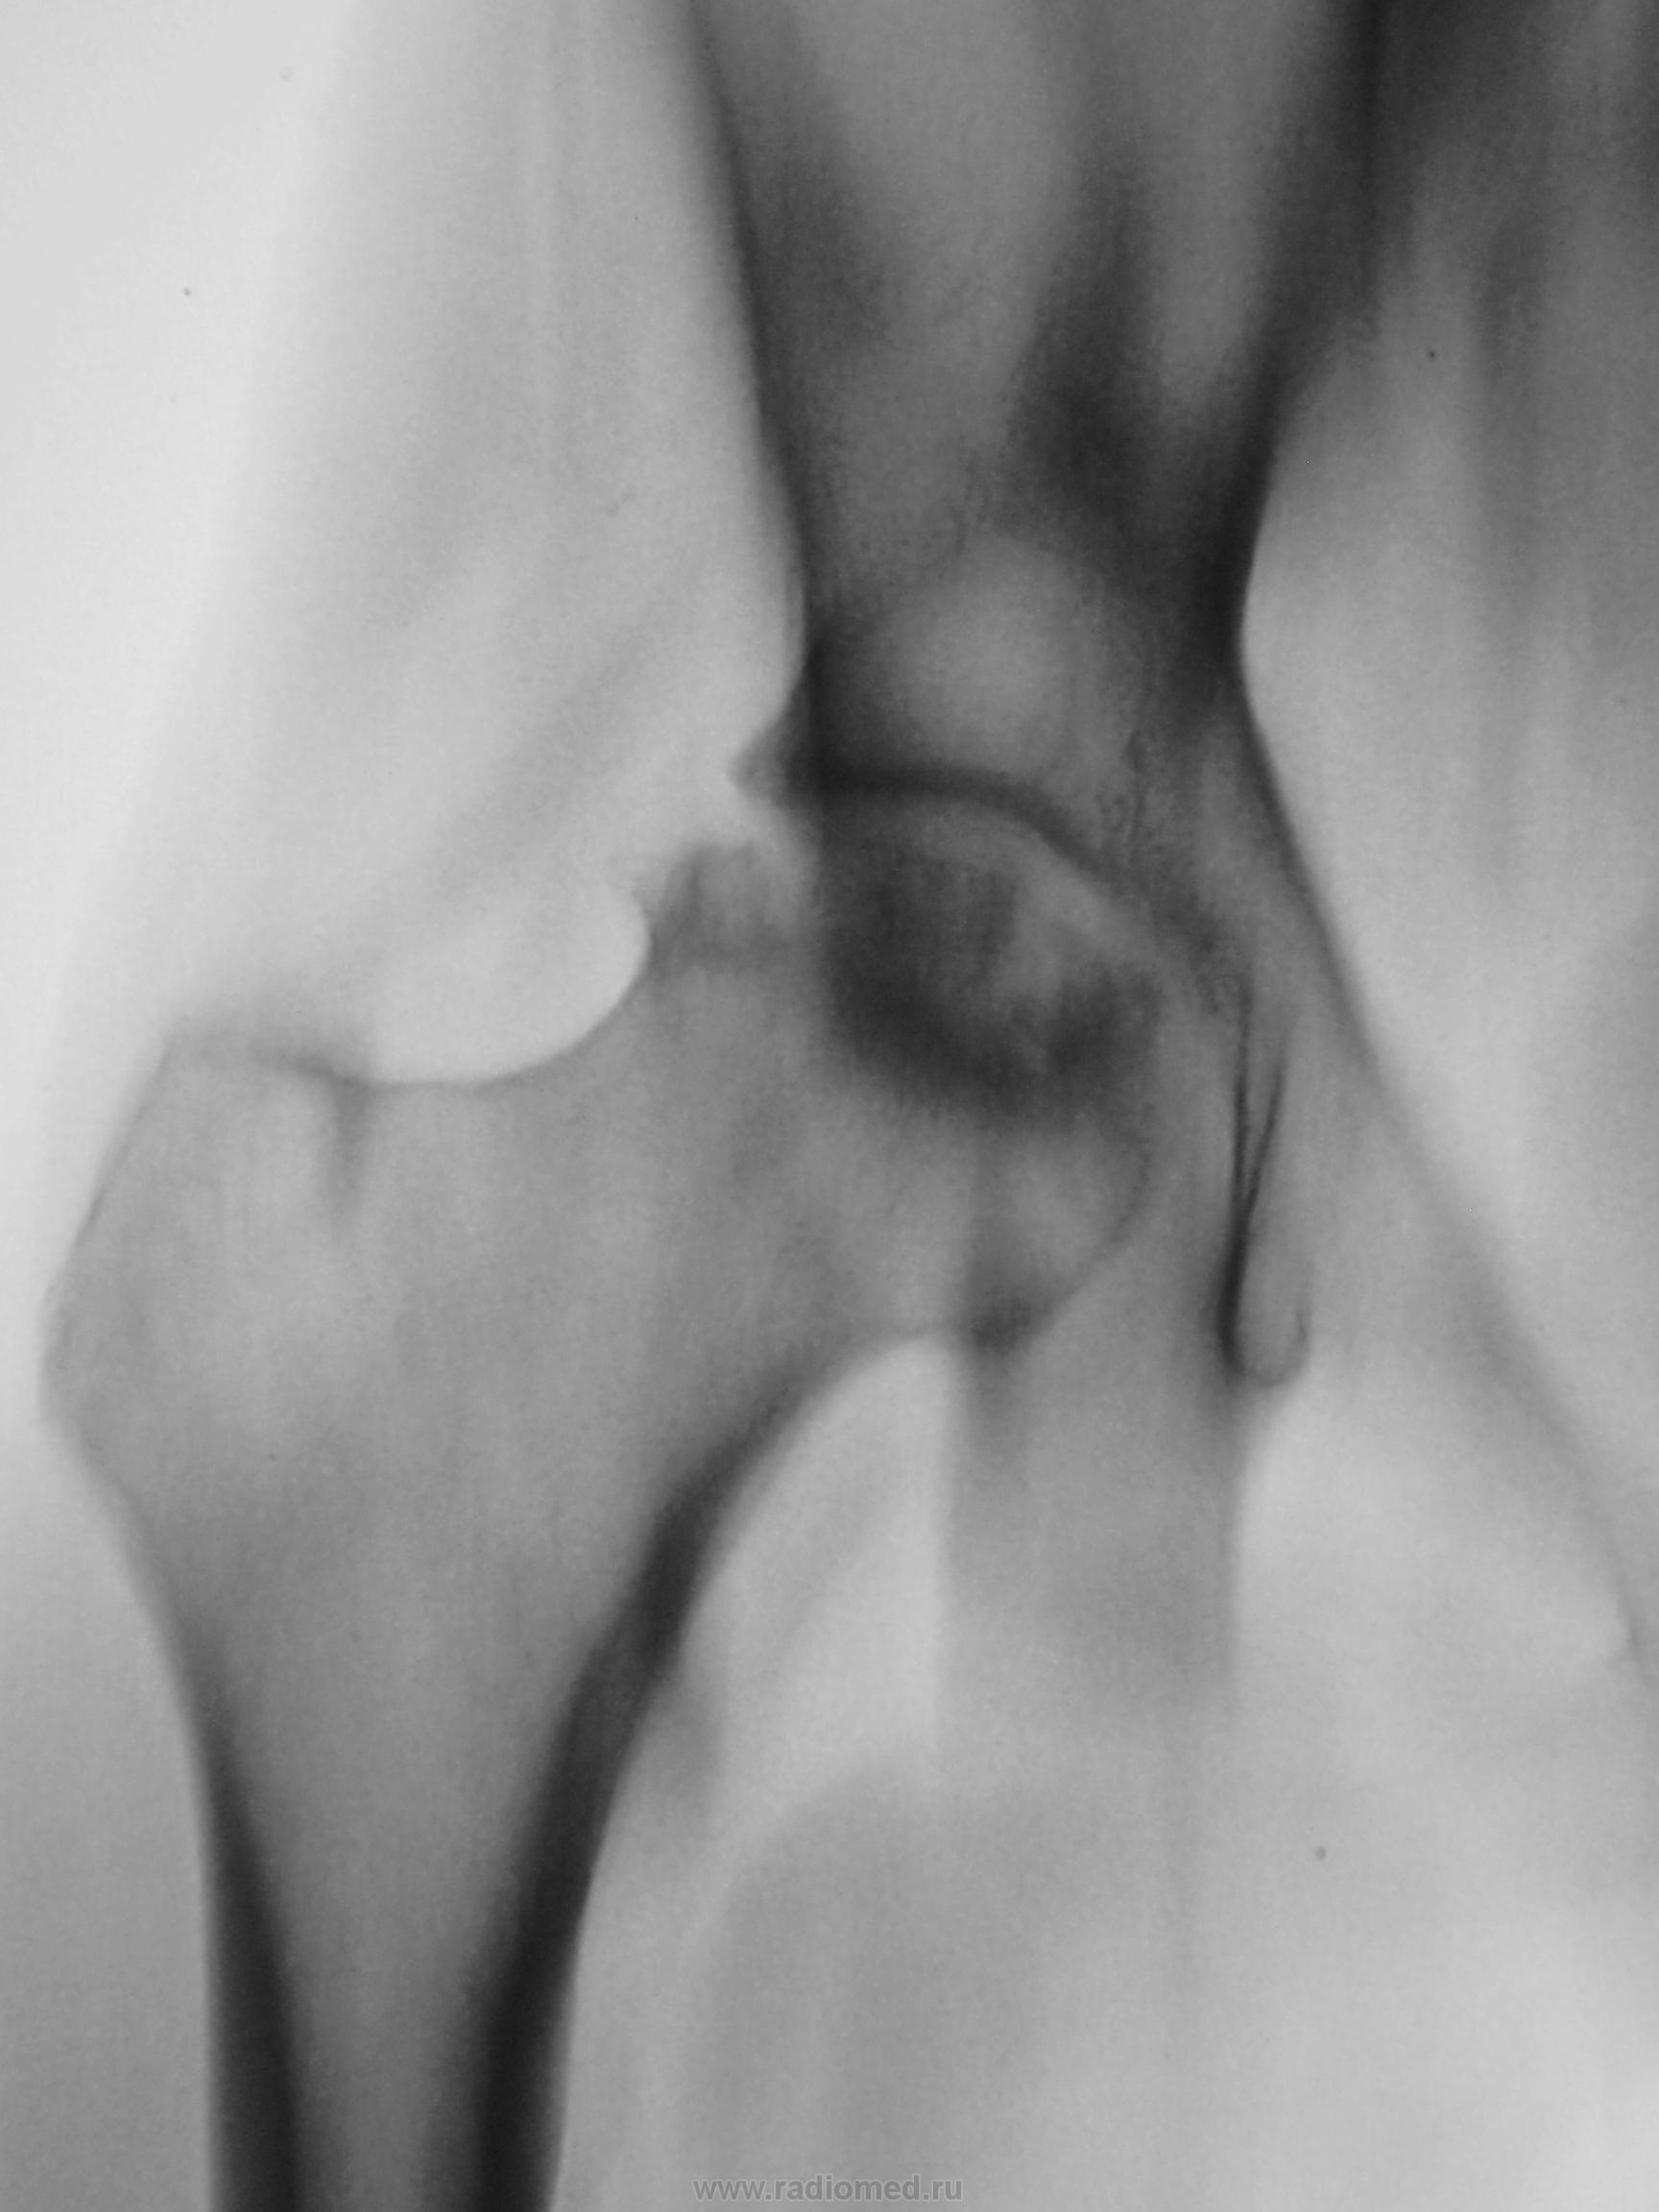

Вот и решили мы, пройтись по суставу линейной томографией, ибо согласия в товарищах не было. Конечно, линейку нельзя сравнить с КТ, но мал-мал картина прояснилась, да и консультанты, одобрительно покивали головами.

Конечно, пациентке было сделано только 4 среза, остальные иллюстрации - это происки АРМа в тесном контакте с ДИКОМОМ.

Отдельно головка.

Приложения: